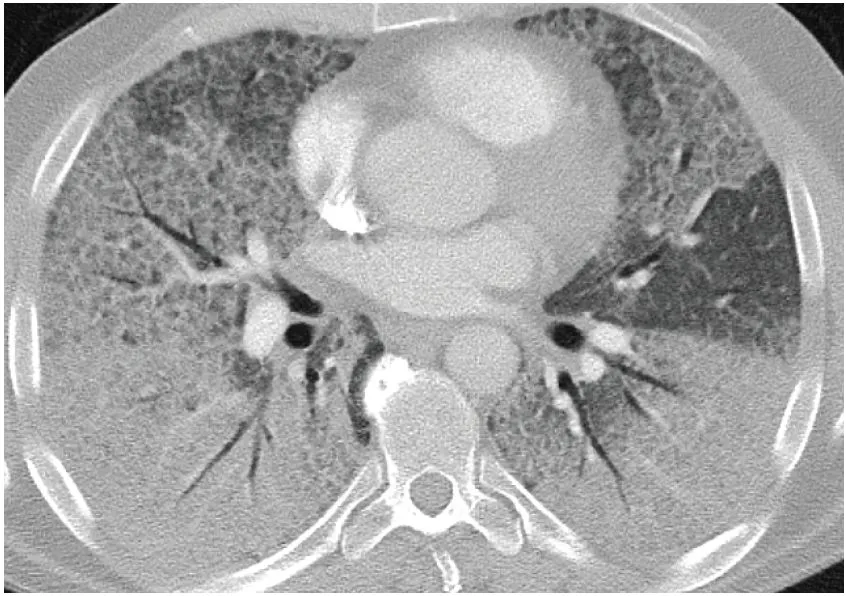

Axial CT shows interlobular {{c1::septal}} thickening in regions of {{c1::groundglass}} opacification, representing {{c2::crazy paving}}

--> This was a case of alveolar proteinosis, the entity in which crazy paving was first described